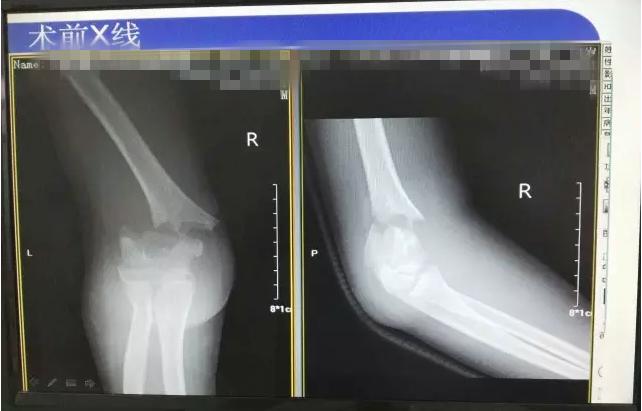

病案二:患儿谭XX,男,14岁,摔伤后右肘关节疼痛伴活动受限5小时入院。

肱骨髁上骨折闭合复位手术记录,小儿肱骨髁上骨折手术恢复的概率 诊断:Gartland III型骨折